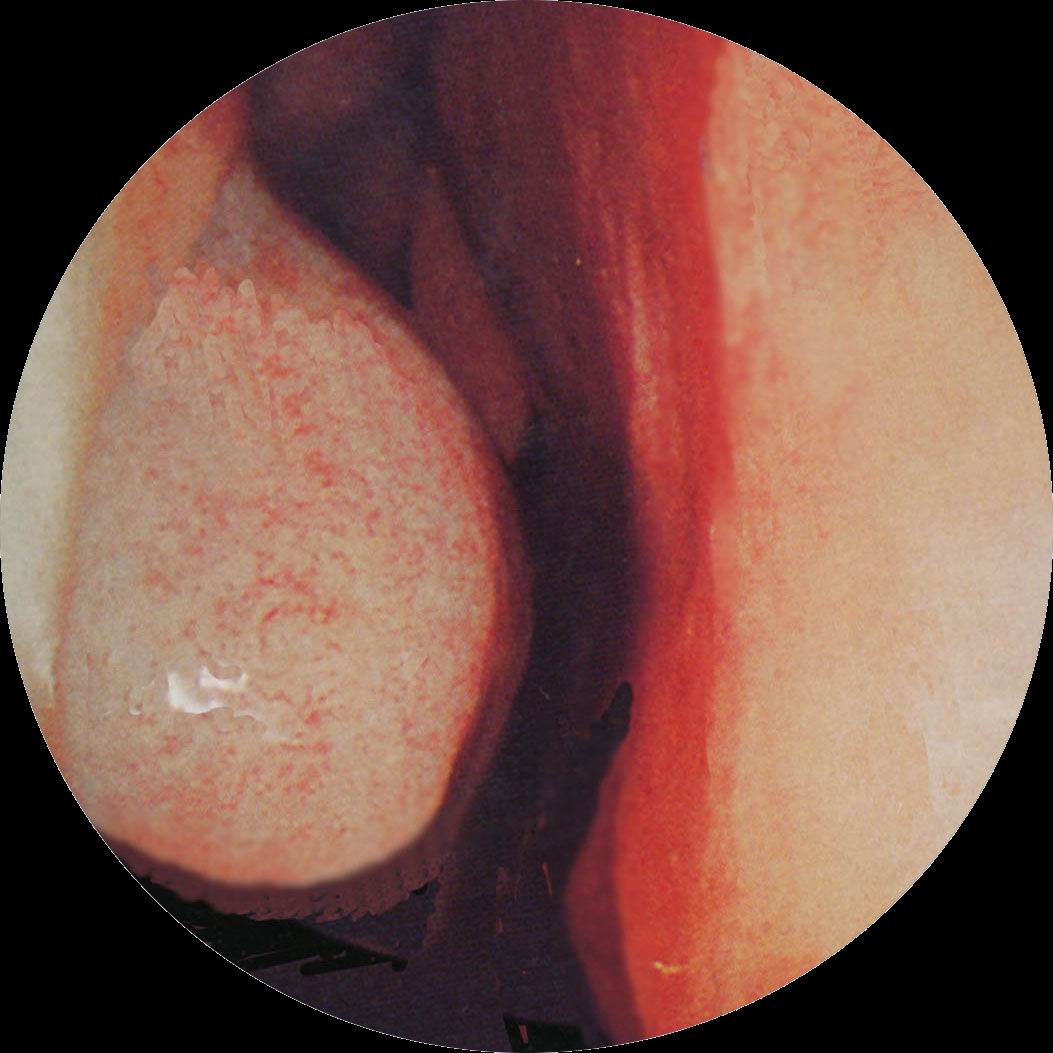

1.鼻塞较重,多为持续性、常张口呼吸,嗅觉多减退。

5.慢性肥厚性鼻炎患者由于鼻呼吸障碍,鼻甲的后端粘膜往往特别肥厚,它不但阻碍呼吸,并且会影响通向中耳的咽鼓管,使患者发生耳鸣和听力减退。由于鼻塞严重,擤出的鼻涕似乎并不太多,鼻涕常向后流入咽内,并不断作擤涕及吸涕的动作。